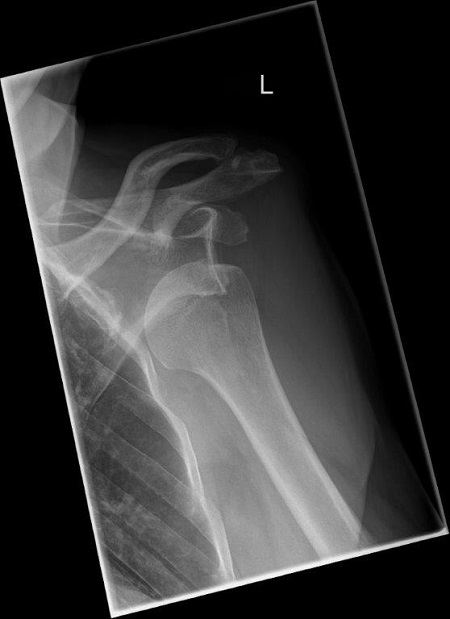

Die Diagnosestellung basiert auf der Krankengschichte (unfallbedingte Verrenkung, einmal oder mehrfaches Auskugeln ...), der Untersuchung der betroffenen Schulter sowie der bildgebenden Diagnostik. Hierbei sind sowohl konventionelle Röntgenbilder, als auch Schnittbildverfahren (MRT – Kapselschaden, CT – knöcherne Verletzung, Defekte) hilfreich. In komplexen Fällen müssen diese durch intraartikuläre Kontrastmitteluntersuchungen ergänzt werden.

69-jähriger Patient mit linkseitiger Schulterluxationsverletzung. Bei älteren Patienten kommt es im Rahmen der Schulterverrenkungen häufiger zu Sehnenabrissen am Oberarmkopf. Trotz der Einrichtung des Gelenkes kann der Arm nicht wieder gut bewegt werden. Erst die operative, in diesem Falle rein arthroskopische Rekonstruktion der Sehnen und deren Einheilen ist eine Schultergelenksbewegung wieder gut möglich.